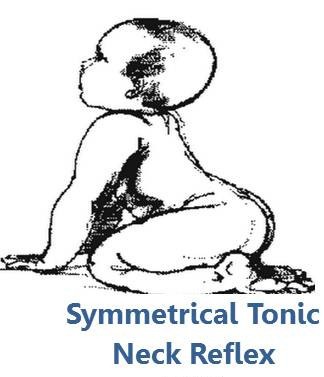

Reflexele primare se dezvoltă intrauterin, sunt prezente la naștere la nou-născuțîi la termen și sunt inhibate de către centrii superiori ai creierului în dezvoltare, în primele șase luni de viață.

Reflexele sunt active în primele 6 luni de viață, însă din momentul nașterii, acestea întră într-un proces de inhibare graduală determinată de centrii superiori ai creierului. În timp ce reflexele primare sunt inhibate, își fac apariția reflexele posturale, acestea dezvoltându-se pe deplin în aproximativ trei ani și jumătate.

Prezența sau absența reflexelor primare sau posturale în anumite etape cheie ale dezvoltării reprezintă argumentul pentru imaturitatea în funcționarea sistemului nervos central și va influența dezvoltarea și controlul posturii, echilibrului și a funcțiilor motorii.